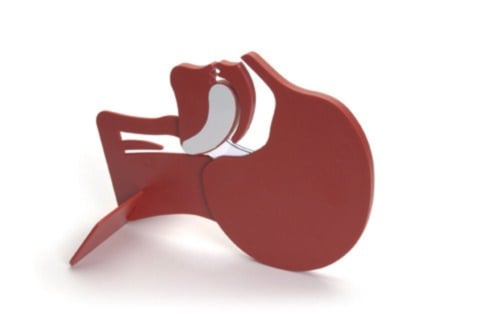

Modèle de tête en coupe

| Nom du produit | Modèle de tête en coupe |

| SKU | 010900 |

Fabricant

Laerdal |

| Poids | 0.4 kgs |